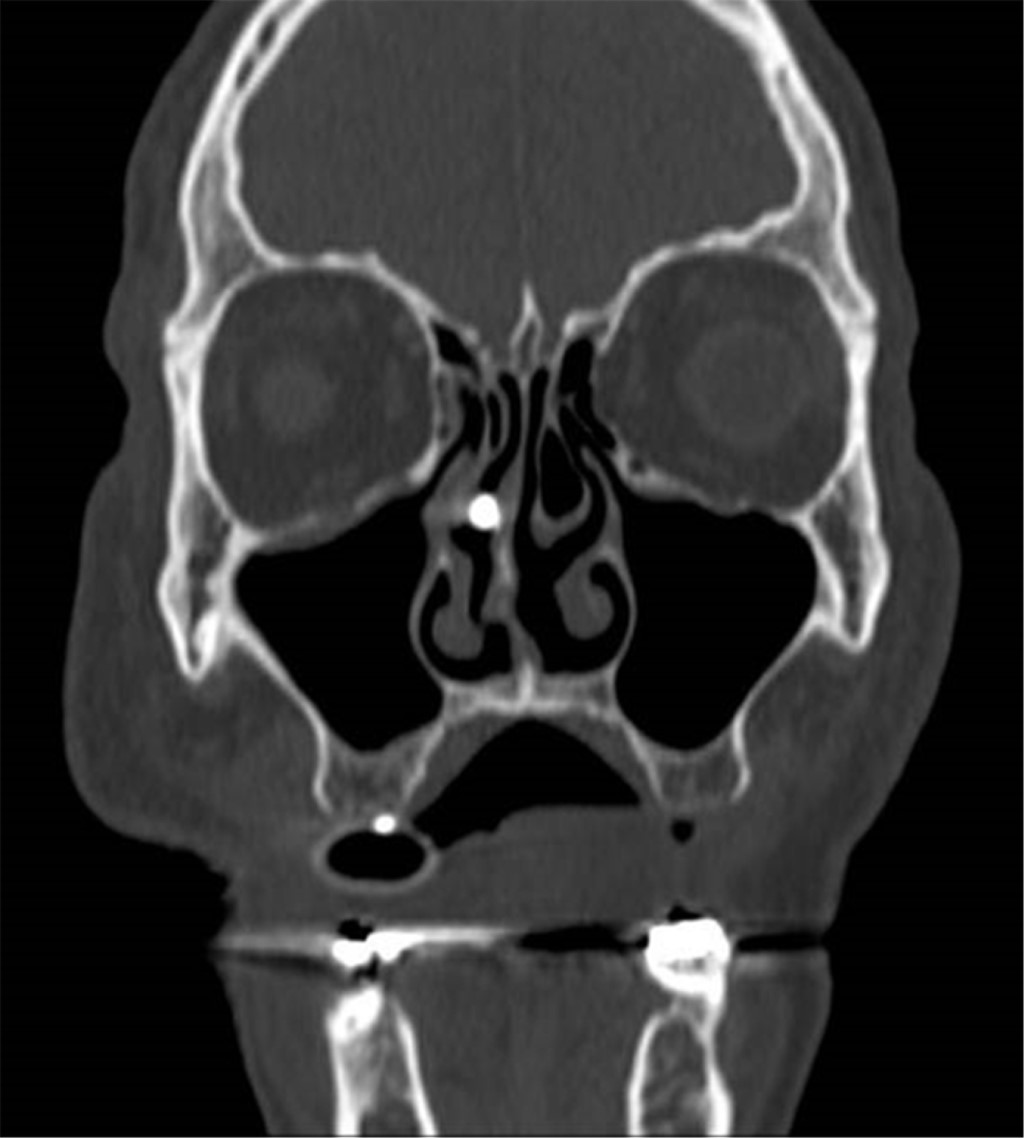

A 69-year-old male patient with a history of type 2 diabetes mellitus was treated with metformin and chlorpropamide. He also had hypertension treated with losartan and amlodipine. He presented to the emergency department with headache, chest pain, cough, myalgias, arthralgias, and dyspnea of one-week evolution. On admission, his heart rate was 114 bpm, respiratory rate 24 rpm, oxygen saturation 80% without supplemental oxygen support; his glucose was 587 mg/dl, white blood cells 25,690 cells/mm3, neutrophils 85%, lymphocytes 1.2%, hemoglobin 16.3 g/dl, procalcitonin 3.78 ng/dl, arterial blood gas with a pH of 7.41, pCO2 21 mmHg, PO2 35 mmHg, HCO3 13 mmol/l, oxygen saturation 62%. A rapid antigen test for SARS-CoV-2 was performed, and the result was positive; a CT scan of the chest showed radiological data suggestive of SARS-CoV-2 infection (Figure 1), and management with supplemental oxygen, insulin infusion pump, carbapenem antibiotics, antihypertensives, dexamethasone, and antithrombotic prophylaxis with enoxaparin was started. 48 hours after admission, the patient continued with septic shock, so vasopressor amines were started; an orotracheal intubation was performed and support with invasive mechanical ventilation was initiated. A nasogastric tube (NGT) was placed. After 24 hours of its placement, he presented hematemesis accompanied by abdominal distension, leukocytosis of 40,000 cells/mm3. A simple abdominopelvic CAT scan was performed, which revealed gastric pneumatosis and pneumoperitoneum (Figure 2). An urgent exploratory laparotomy was performed finding necrosis of the greater curvature of the stomach. A vertical gastrectomy was performed with GIA stapler with purple cartridges of 45 and 60 mm (Figure 3); the stapling line was reinforced with continuous a Prolene suture 00; a feeding jejunostomy tube was placed at 60 cm from the Treitz angle and Saratoga drains were left in place. Twenty-four hours later, the patient had hemodynamic stability, vasopressor amines were suspended, and enteral nutrition with an elemental diet was started. On the fifth postoperative day, the patient showed adequate tolerance to the enteral diet through jejunostomy. The methylene blue test was performed through the nasogastric tube showing no evidence of leaks; the white blood cell count decreased to 24,000 cells/mm3. Histopathology results were obtained revealing pan mural necrosis associated with arterial thrombosis secondary to microorganisms compatible with Mucor sp.; therefore, management with amphotericin B was initiated (Figures 4 and 5). During follow-up he showed good evolution; an abdominopelvic CT scan with contrast by the nasogastric tube was performed, which ruled out leaks and intra-abdominal collections and corroborated the integrity of the gastric wall; drains were removed, and the patient was discharged from general surgery on day 9 post-surgery, continuing to be managed by the internal medicine service. During the following days of hospitalization, the patient presented cardiovascular and pulmonary deterioration; a urine culture was taken, which showed growing of Candida tropicalis, and a CAT scan of the skull, thorax, and abdominopelvic with oral contrast was performed (Figures 6 and 7), The patient continued without evidence of abdominal leaks, rhino-cerebral and pulmonary mucormycosis were ruled out. A probable superimposed bacterial pneumonia and interstitial pneumopathy secondary to COVID-19 were reported. He showed persistent clinical deterioration and refractory shock and 29 days after admission.

Figure 1